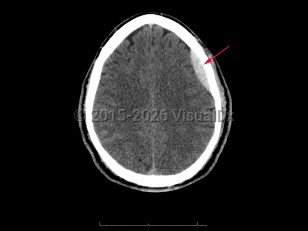

Idiopathic intracranial hypertensionIdiopathic intracranial hypertension